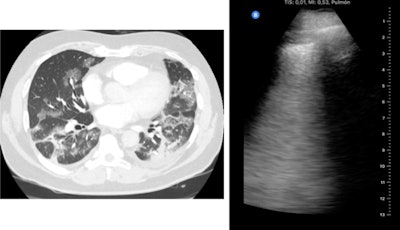

Out of the 51 patients in the study, 37 patients had findings suggestive of COVID-19 on CT and 40 had COVID-19-like findings on ultrasound. Statistical analysis revealed significant agreement between lung ultrasound and CT findings, including an ultrasound sensitivity of 100%, specificity of 79%, and positive predictive value of 93%.

Patients' lung ultrasound scores also had good correlation with their CT severity scores. Both LUS and CT scores were strongly correlated with patients' oxygen saturation, respiratory rate, and inflammatory markers, although the relationship was stronger for ultrasound.